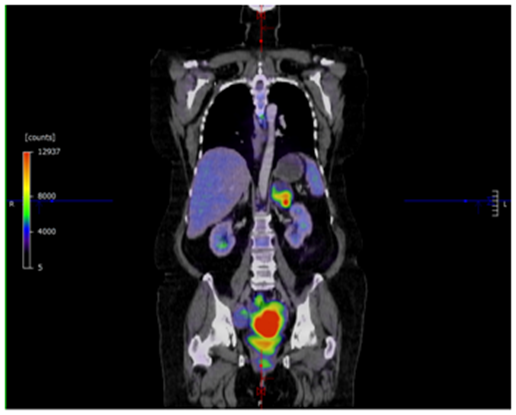

A 52 year old G1P1001 female with a history of hypertension, hyperlipidema, depression, and schizoaffective disorder presented with the primary complaint of a painful left sided vaginal mass. She also complained of irregular heavy menses for the past three months. On pelvic exam, the vaginal mass was diagnosed as a left Bartholin gland abscess that measured 2x3cm and was noted to be indurated. The remainder of the pelvic exam was unremarkable. The patient was offered incision and drainage for which she declined. She was started on Augmentin. Perimenopause was thought to be a contributing factor of the patient’s irregular menstrual pattern. As part of screening guidelines, Papanicolaou smear was performed and was found to be remarkable for atypical glandular cells of undetermined significance. Endometrial biopsy (EMB) was recommended. The patient was lost to follow up for two months. She eventually returned to clinic and reported improvement in the abscess after antibiotics, but recurrence after discontinuation. During her follow up visit, EMB and incision & drainage of the Bartholin abscess with placement of Word catheter was performed. However, due to the exuberant amount of indurated tissue expressed from the Bartholin abscess, a tissue specimen of the Bartholin abscess were sent to pathology for evaluation. The pathology report returned a poorly differentiated malignant neoplasm favoring carcinoma for the Bartholin gland sample as well as the endometrial biopsy sample. The tumor was described as poorly differentiated and consisting of enlarged nuclei with vesicular chromatin, perinuclear clearing, occasional prominent nucleoli, moderate amounts of amphophilic delicate cytoplasm, and increased mitoses (Figures 1 & 2). There was also extensive tumor necrosis seen in the specimens (Figure 3). The patient underwent CT of her chest, abdomen, and pelvis, as well as a PET CT of the skull to thigh. Her CT revealed a 10.8 cm poorly defined endometrial and myometrial neoplasm, with metastatic disease to the right iliac node, right parametrial nodes, periaortic lymph nodes, and bilateral adrenal glands. There were no other significant findings on CT. Her PET scan showed prominent Fluorodeoxyglucose (FDG) activity in the uterine mass and left adrenal mass, with a smaller amount of FDG activity in a large right pelvic lymph node adjacent to the uterine mass, with no other contributory findings (Figure 4). She was referred to the care of medical oncology, and during the patient’s Gynecology Tumor Board case presentation the pathologists concluded that her poorly differentiated cancer was uterine in origin. Due to the extent of metastatic disease she was recommended medical management. She was started on a Paclitaxel and Carboplatin chemotherapy therapy.

Figure 4 PET scan showing many areas of FDG avidity. There is a large area of FDG activity in the area of the uterine cancer mass, with activity also present in the left adrenal mass.